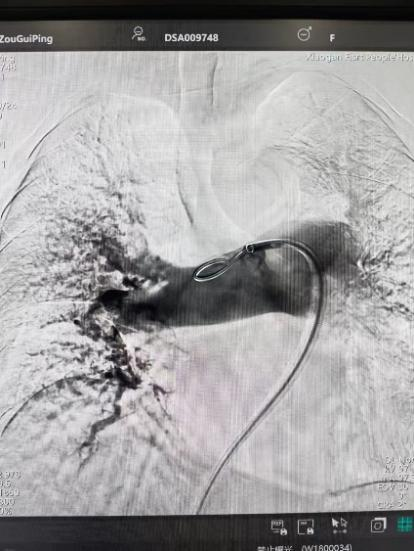

術(shù)前

手術(shù)在局部麻醉下進(jìn)行,團(tuán)隊(duì)通過股靜脈穿刺,將專用抽栓導(dǎo)管精準(zhǔn)送達(dá)肺動脈栓塞部位,利用負(fù)壓抽吸技術(shù)成功清除大量血栓;隨后,在血栓局部精準(zhǔn)灌注溶栓藥物,進(jìn)一步溶解殘余血栓,恢復(fù)肺部血流灌注;同時,為防止下肢深靜脈血栓再次脫落引發(fā)肺栓塞,團(tuán)隊(duì)為患者置入下腔靜脈濾器,整個手術(shù)歷時約1小時。術(shù)后,鄒婆婆呼吸困難癥狀即刻得到緩解,血氧飽和度顯著提升,右心負(fù)荷明顯減輕,目前身體狀況正在逐步恢復(fù)中。